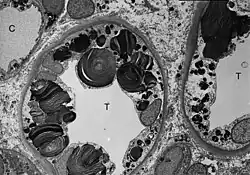

Wie die meisten Symptome bei Morbus Fabry weist auch die Schädigung der Nieren einen progressiven Verlauf auf. Er endet mit dem terminalen Nierenversagen und bewirkt eine deutlich reduzierte Lebenserwartung.[70] Bei dem klassischen Krankheitsbild des Morbus Fabry führen die Gb3-Ansammlungen in den Endothelzellen des Glomerulums, in den Mesangiumzellen, in den Podozyten und in den Zellen des Interstitiums zur Schädigung der Niere.[71] Bei diesen Zellen handelt es sich um ausdifferenzierte Epithelzellen. Auch im Epithel der Henle-Schleife und des distalen Tubulus sowie im Endothel und den Zellen der glatten Muskulatur der Arteriolen der Niere finden sich Glycosphingolipid-Ansammlungen.[72][73] Im Transmissionselektronenmikroskop (TEM) sind die Gb3-Ablagerungen im Zytoplasma gut zu erkennen. Sie haben die Form von Myelinstrukturen und stoßen an den Zellkern. Mit zunehmender Gb3-Akkumulation wird das Mesangium aufgeweitet, worauf eine segmentale oder globale Glomerulosklerose mit Eindickung der Basalmembranen erfolgt.[74] Mikrovaskuläre Läsionen und Schädigungen der für die Filterleistung wichtigen Podozyten sowie der Epithelzellen des Tubulus werden dabei als mögliche Mechanismen diskutiert.[75]

- Gewebeproben aus der Niere von Patienten mit Morbus Fabry

-

Diese lichtmikroskopische Aufnahme zeigt die Akkumulation von Gb3 in den Endothelien des Glomerulums, in den Mesangiumzellen, den Zellen im Interstitium und in den Podozyten. -

Ebenfalls eine lichtmikroskopische Aufnahme. In den Podozyten ist die erhöhte Ansammlung an Gb3 durch eine violette Anfärbung sichtbar gemacht worden. -

Die TEM-Aufnahme zeigt die massive elektronendichte (= schwarze) Ansammlung an Glycosphingolipiden im Lysosom der Podozyten. -

Ebenfalls eine TEM-Aufnahme. Sie zeigt die Inklusionen von Glycosphingolipiden unterschiedlicher Form und Größe in den Zellen des distalen Tubulus. -

TEM-Aufnahme von den Endothelien und Zellen der glatten Muskulatur einer Nierenarteriole mit Inklusionen von Glycosphingolipiden